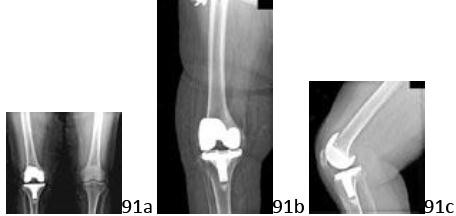

2. # Figure 4 shows the radiograph of a 65-year-old patient who is undergoing right total knee arthroplasty. After performing bone resections for a posterior cruciate-substituting femoral component, you note that both the flexion and extension gaps are tight in the lateral compartment. Which of the following structures should be released

first?

DISCUSSION: For patients with tightness in both flexion and extension, the lateral collateral ligament should be released before the other lateral structures. Soft-tissue balancing after correction of a

valgus deformity is performed to equalize varus and valgus laxity in both flexion and extension. If it is released after the other stabilizers (iliotibial band, posterolateral capsule, or popliteus tendon), the magnitude of these corrections will be more significant. This may lead to a greater flexion-extension asymmetry if an isolated extension or flexion release has been performed first. Release of the posterior cruciate ligament has the greatest impact on lateral knee balance, so the decision to use a cruciate retaining or substituting implant ideally should be made before proceeding with release of the lateral structures. An isolated flexion contracture is typically approached with a posterolateral capsule release. An isolated extension contracture may be treated with either a release of the iliotibial band or popliteus tendon. However, authors recently have indicated a preference for retention of the popliteus tendon. The Preferred Response to Question # 4 is 2.